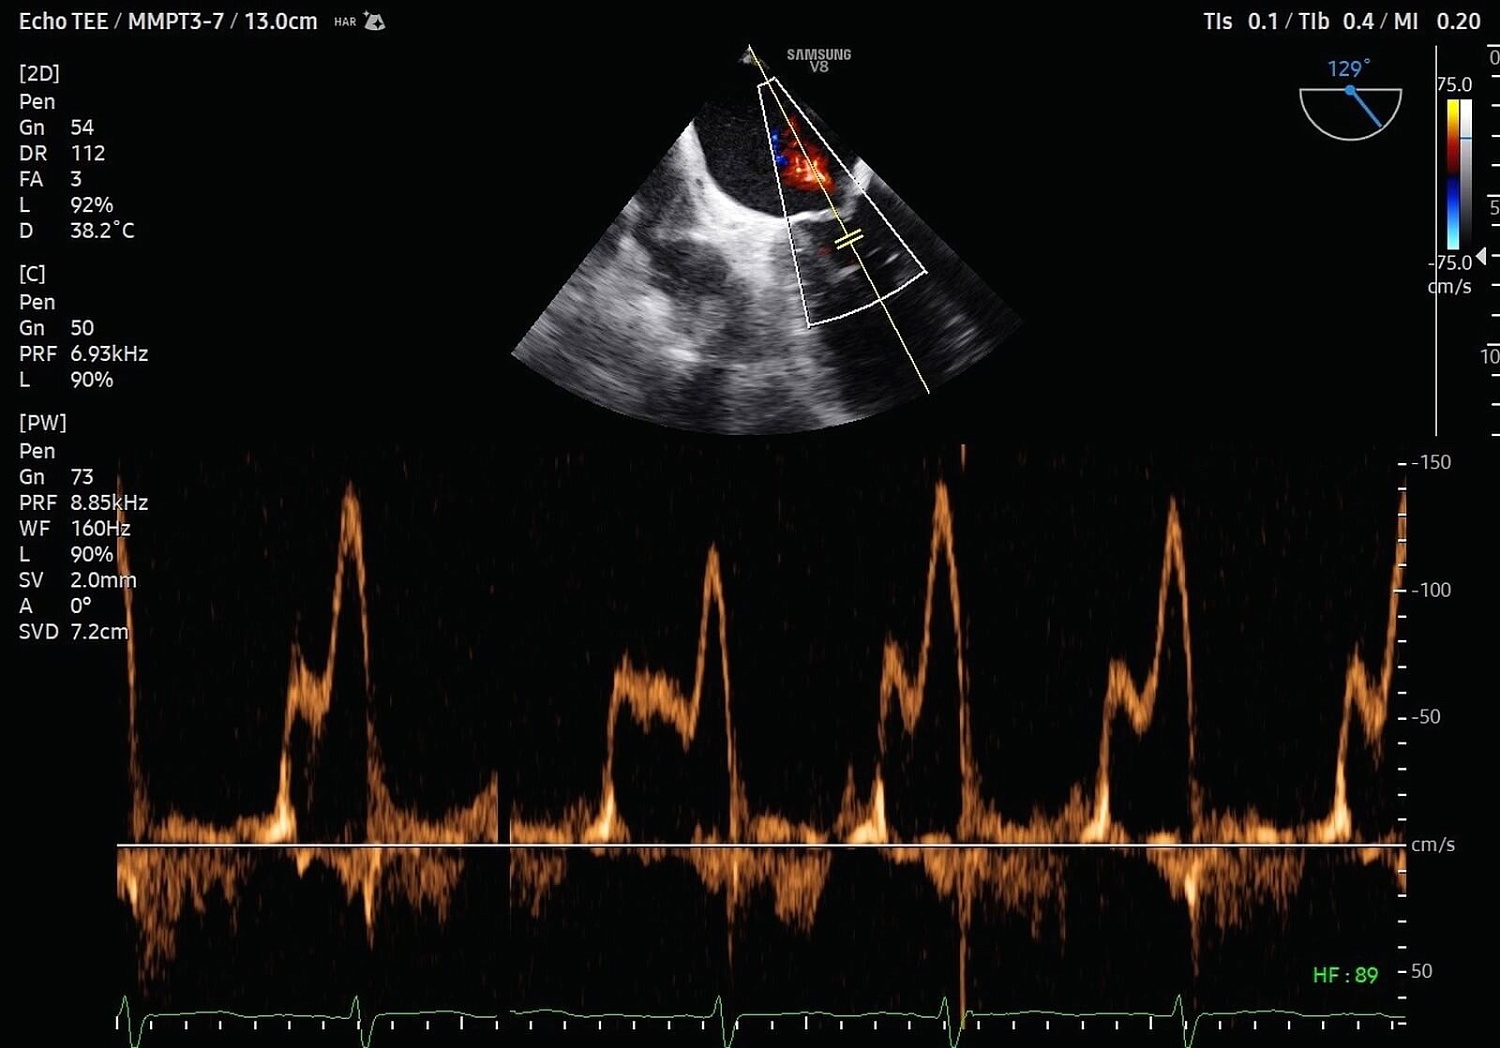

Рады сообщить, что в ассортименте нашей компании появился ультраинновационная УЗИ система экспертного (премиального) класса Samsung Medison V8. Этот ультразвуковой аппарат, функционирующий на базе искусственного интеллекта, предназначен для проведения исследований любого уровня сложности в области онкологии, пренатальной диагностики, неонатологии, гинекологии, урологии, а также общей радиологии, ортопедии, кардиологии и ангиологии.

УЗИ аппарат V8 отличается превосходным технологическим оснащением, высочайшим уровнем визуализации и удобством использования. Многочисленные решения позволяют оптимизировать рутинный диагностический процесс, автоматически осуществляя измерения, расчеты и классифицируя выявленные изменения. Это значительно сокращает время на исследование и в разы повышает диагностическую точность. Помимо уже знакомых функций Biometry Assist, AutoIMT, 2D Follicle, 2DNT и пр., в модели реализована опция автоматического сегментирования структур сердца, автоизмерения с технологией Heart Assist, определение положения срединного нерва в поперечном сечении Nerve Track.